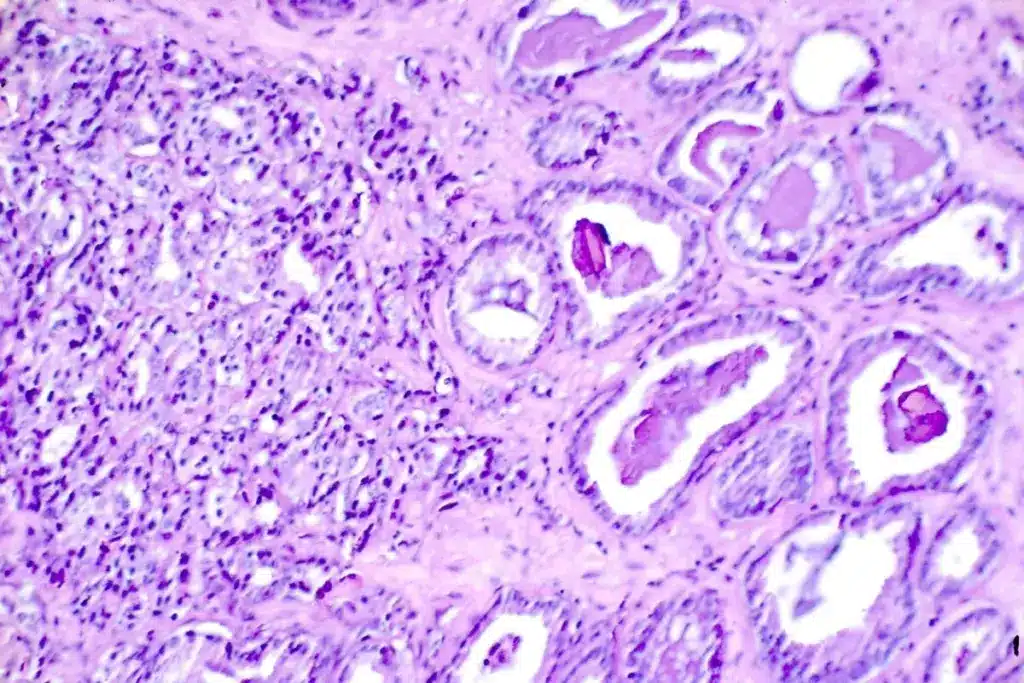

- Biopsy: It checks tissue samples for cancer cells.